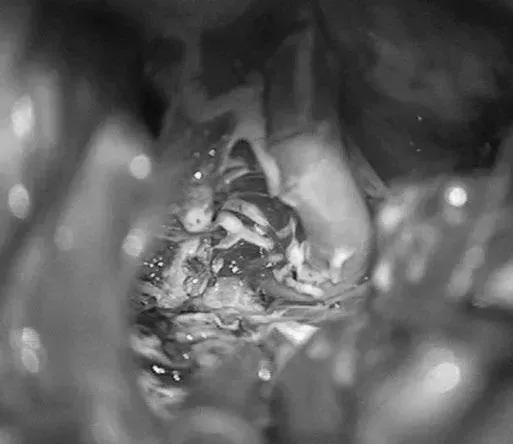

▼右侧眶颧开颅,经侧裂入路,牵开颞较暴露来自ICA鞍上段、MCA的M1段、PCA的P2段和小脑幕切迹。

(a)1步:使用眶颧入路垂直显示AVM,经侧裂分离,就像前往基底动脉分叉动脉瘤的入路。

(b)2步:移除眶骨可以比翼点入路提供更靠前的径路,使术野可以延伸到颞叶内侧表面。卸下颧弓以便颞叶向后外侧回缩,进一步拓宽术野。向后外侧回缩显露颞叶内侧面,使之成为一个凸面的入路。总的来说,眶颧开颅缩短了到达AVM的工作距离,并增加显露。分离侧裂将颞叶内侧面从粘连的额叶上分开,打开颈动脉池和脚间池,分离围绕钩回的AChA。